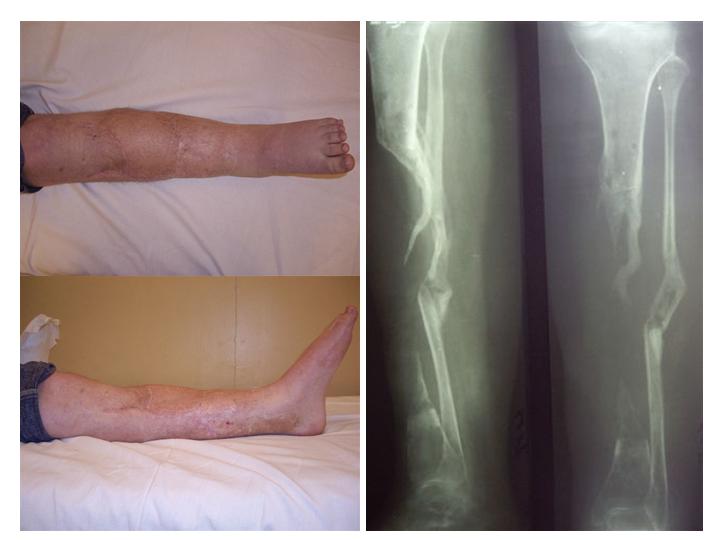

Отправлено Ласунский Сергей 30 Октябрь 2007, 23:53 РОСНИИТО им.Р.Р.Вредена

Пациентка с дефектом большеберцовой кости, возможно ли восстановление опороспособности нижней конечности? ДТП 1.5 года назад: открытый оскольчатый перелом средней трети левой голени с дефектом мягких тканей. Выполнены следующие операции в одной мз больниц города: 1.При поступлении ПХО и наложение АВФ 2.Нагноение резекция нежизнеспособной кости. 3.Пластика дефекта мягких тканей. 4.Попытка устранения дефекта по методу Илизарова, нагноение, радикальная хирургическая обработка, увеличение дефекта. 6 месяцев без признаков гнойного воспаления. В настоящее время иммбилизация гипсовой лонгетой до коленного сустава, функция коленного сустава сохранена, голеностопного нет.

Уважаемый Александр! Привет из Питера. Спасибо за быстрый ответ. Стержень с блокированием и кейдж, вариант изветный по литеоатуре, но очень короткий дистальный фрагмент и локальный остеопороз (будет ли хорошая фиксация?). Как считаешь вариант с фиксацией ложного сустава малоберцовой кости спластиной и ее предварительное утолщение свободным аутотрансплантатом 1\2 малоберцовой кости со здоровой стороны длиной 20-25 см., а после консолидации тибиализация малоберцовой кости?